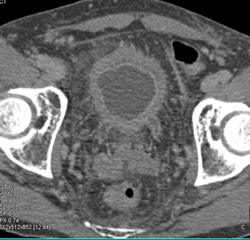

Bladder Cancer